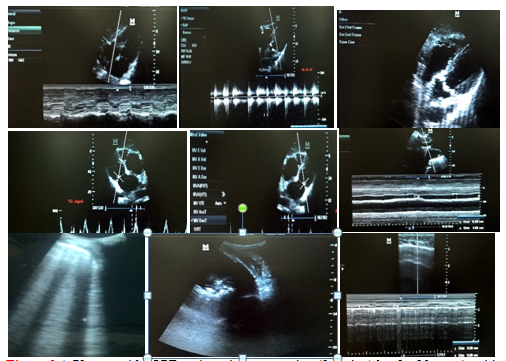

Furthermore, this results were in agreement with the results of Vincent et al.,17 which was conducted in the ICU of two University hospitals, and showed that both the increase of E/A, (ratio of maximal mitral E wave and A wave velocities) (P = 0.003) and shortened DTE (deceleration time of mitral E wave) (P = 0.00001) during the SBT suggest that altered LV diastolic properties may potentially contribute to the rise in LV filling pressure. Ankush et al.,18 reported that echocardiography can help in both prognosis and follow up of patients on MV. In the current study, elevated RVSP was the most frequent ultrasonographic finding (69%) in SBT failure group, Figure 1-3 followed by left ventricular diastolic dysfunction (61.5%), low EF% (38%).19

Figure 1 This figure shows that elevated RVSP (right ventricular systolic pressure) was the most frequent ultrasonographic finding (69%) in SBT failure group, followed by left ventricular diastolic dysfunction (61.5%), low EF% (38%), the B lines (61.5%) , and diaphragmatic thickness index < 20% (19.3%).

Figure 2 A 70- year old COPD female patient, , ex smoker (0.5 pack / day for 40 years), with diabetes mellitus and hypertension, and history of previous mechanical ventilation one year ago. Duration of present mechanical ventilation 10 days, failed weaning twice, at third trial of SBT: chest ultrasound was normal, diaphragmatic thickness index =52 %, EF 53 %, grade 1 diastolic dysfunction, RVSP 40 mmHg with mild TR, normal size of right side of heart, TAPSE = 2.8 cm, IVC collapsibility index = 50%, normal lower limb venous ultrasonography. The SBT was successful, and the patient was weaned from MV.

Figure 3 A 72 -year old COPD male patient, ex smoker (2 packs / day for 20 years), with diabetes mellitus, hypertension and ischemic heart disease, and history of previous mechanical ventilation once 2 years ago. Duration of present mechanical ventilation was 25 days. The patient failed weaning for 10 times. The current SBT was done while on tracheostomy tube. Chest ultrasound showed right lower lobe consolidation and mild pleural effusion, B lines was evident over of anterior lung areas, diaphragmatic thickness index = 33 %, EF 48 %, grade 3 diastolic dysfunction, RVSP 65 mmHg with moderate TR and MR, dilated right side of heart, TAPSE = 1.1cm, IVC collapsibility index = 60 %, and normal lower limb venous ultrasonography. The SBT failed. Recommendations based on US findings included intensifying/ changing antimicrobial regimen, and intensifying /modifying anti-failure and anti-ischemic measures.